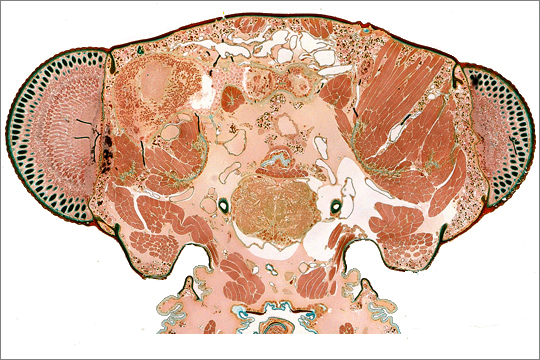

Die Leica Slide-Scanner Einheit ist ein mit MetaMoph-Software gesteuertes, vollautomatischen DM6000 Forschungsmikroskop mit dem bis zu vier Standardobjektträger auf einmal digitalisiert werden können. Da das System Bilder automatisch aus mehreren Aufnahmen zusammensetzt ist die verwendete Vergrößerung (1,25x - 100x) nicht mehr von der Größe des Objekts abhängig sondern kann frei gewählt werden.

Die speziell für histologische Serienschnitte konzipierte Software erlaubt nahezu vollautomatisches Digitalisieren inkl. Schnitterkennung, Autofokus und Aufnahmennummerierung. Bei schwierigen Proben kann die Software aber auch semi-automatisch (z.B. mit manueller Festlegung der Einzelschnitte) oder vollständig manuell (inkl. manuellen Fokus) eingesetzt werden. So wird immer ein optimales Ergebnis erzielt.